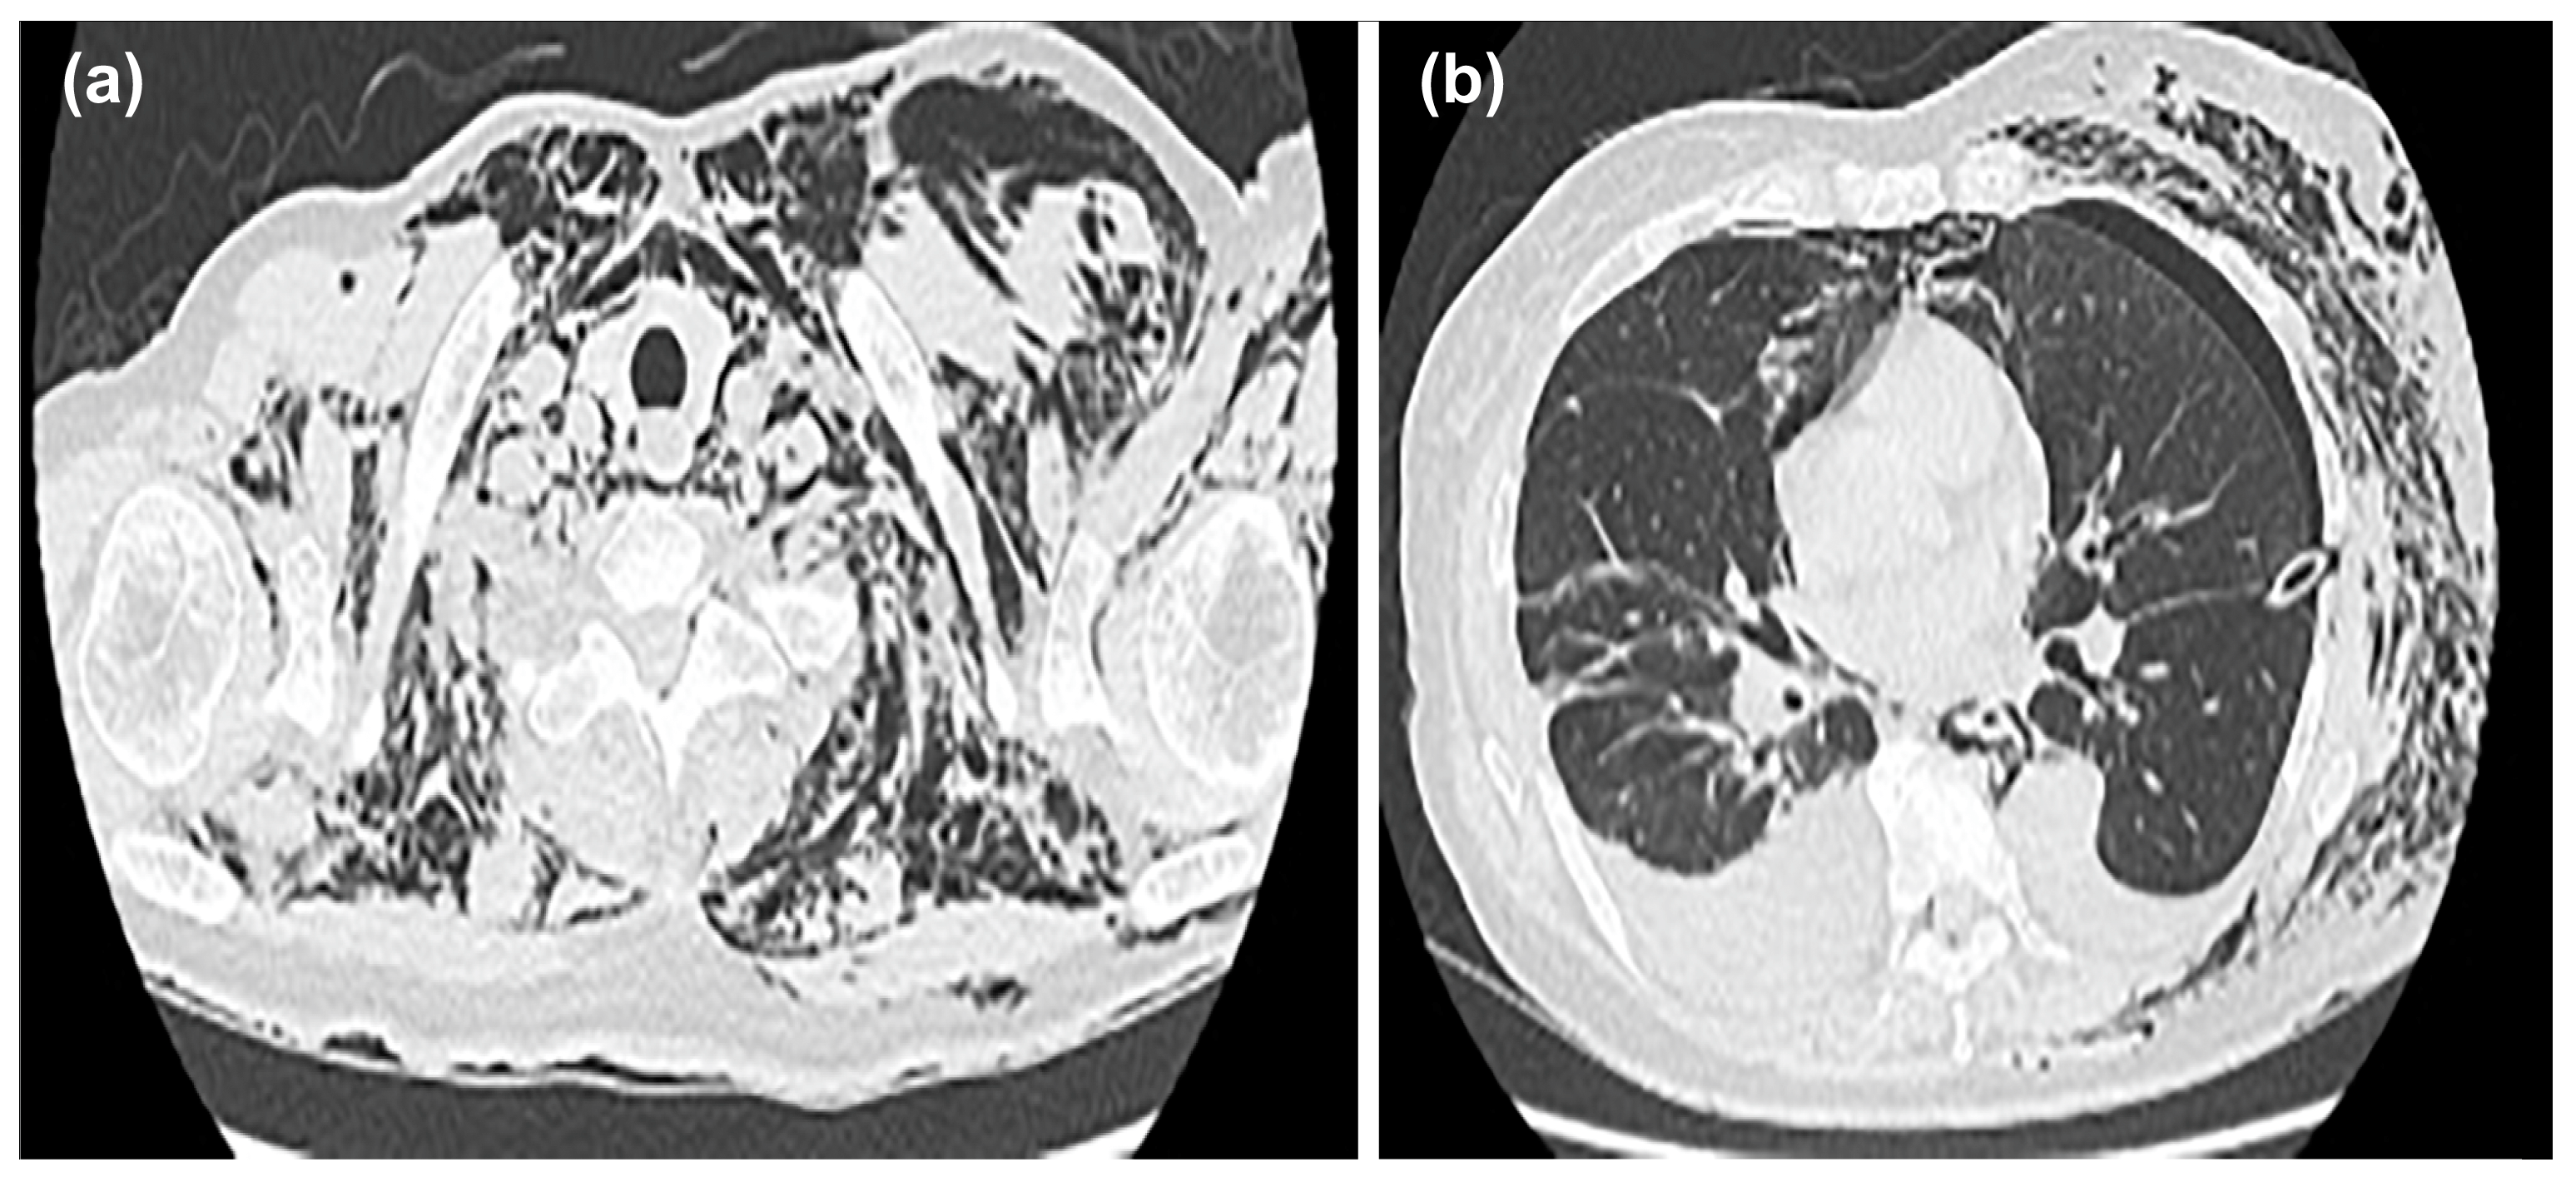

After insertion of the thoracic drain, a chest CT was performed; the scan showed mediastinal emphysema in the anterior mediastinum, with predominant subcutaneous emphysema in the left chest (Figure 3a,b).

Figure 3.

Mediastinal emphysema was observed in the anterior mediastinum, and subcutaneous emphysema was predominant on the left side of the chest (a). A drain was inserted between the lobes in the left thoracic cavity (b).